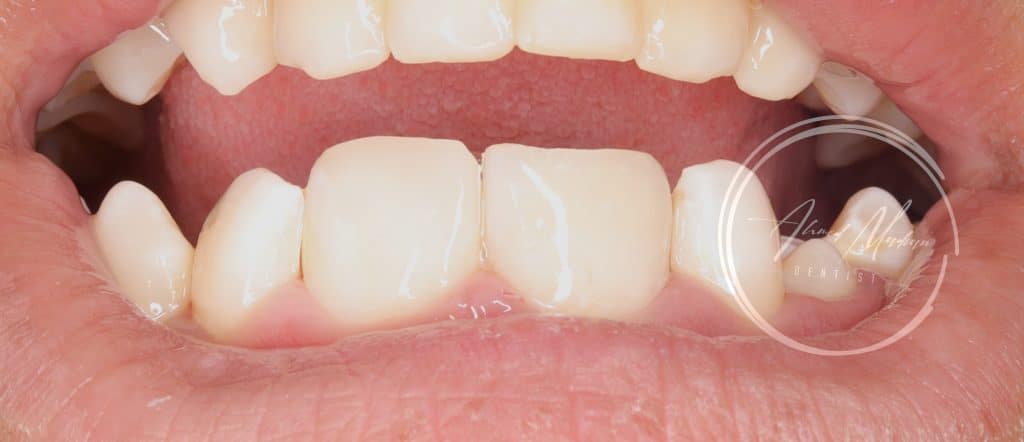

12 – direct composite restoration

Now patient situation is stabilized and will under go regular follow ups and will be referred to orthodontist for further assessment